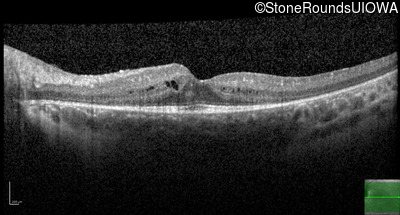

Age at visit: 11 years